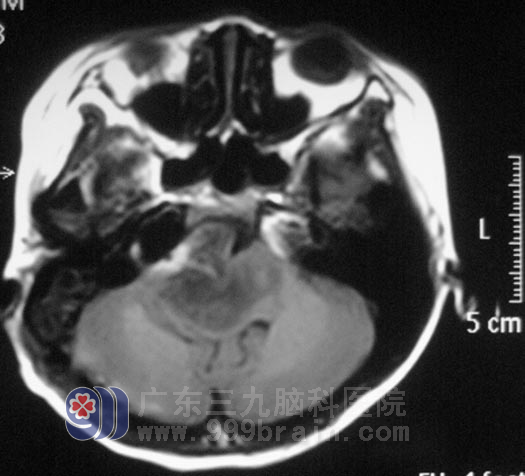

经过治疗,妮妮未出现后组颅神经损害的症状,听力、双眼活动较前好转,视物基本正常。术后病理结果为:间变型星形细胞瘤 WHO III级。

▲手术后